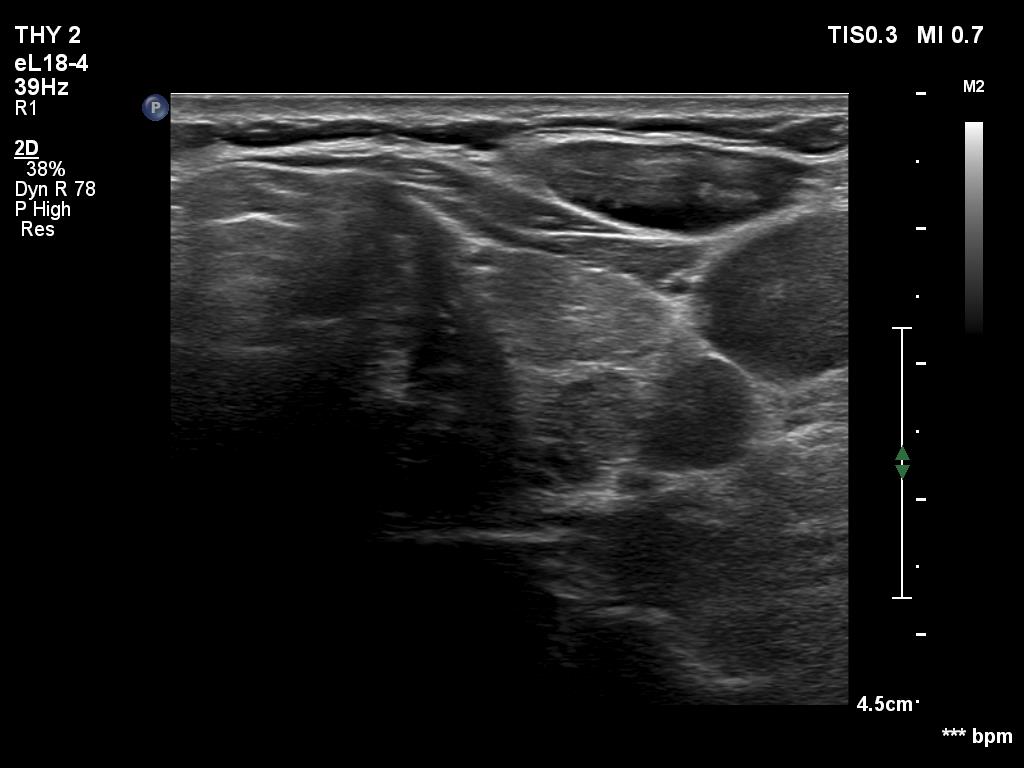

Clinical data: A 61-year-old woman was referred for preoperative localization of a parathyroid adenoma. The patient has been treated for hypothyroidism for seven years. Recently, hyperparathyroidism was diagnosed on evaluation of osteoporosis. MIBI scintigraphy disclosed increased uptake according to one of the left parathyroids.

Ultrasonography. The thyroid was moderately hypoechoic. There were two discrete lesions in the right lobe while a hypoechoic mass was found dorsal to the middle third of the left lobe.

During surgery, intraoperative parathormone measurement disclosed elevated levels according to the left upper parathyroid which has been removed. Histopathology: parathyroid adenoma.